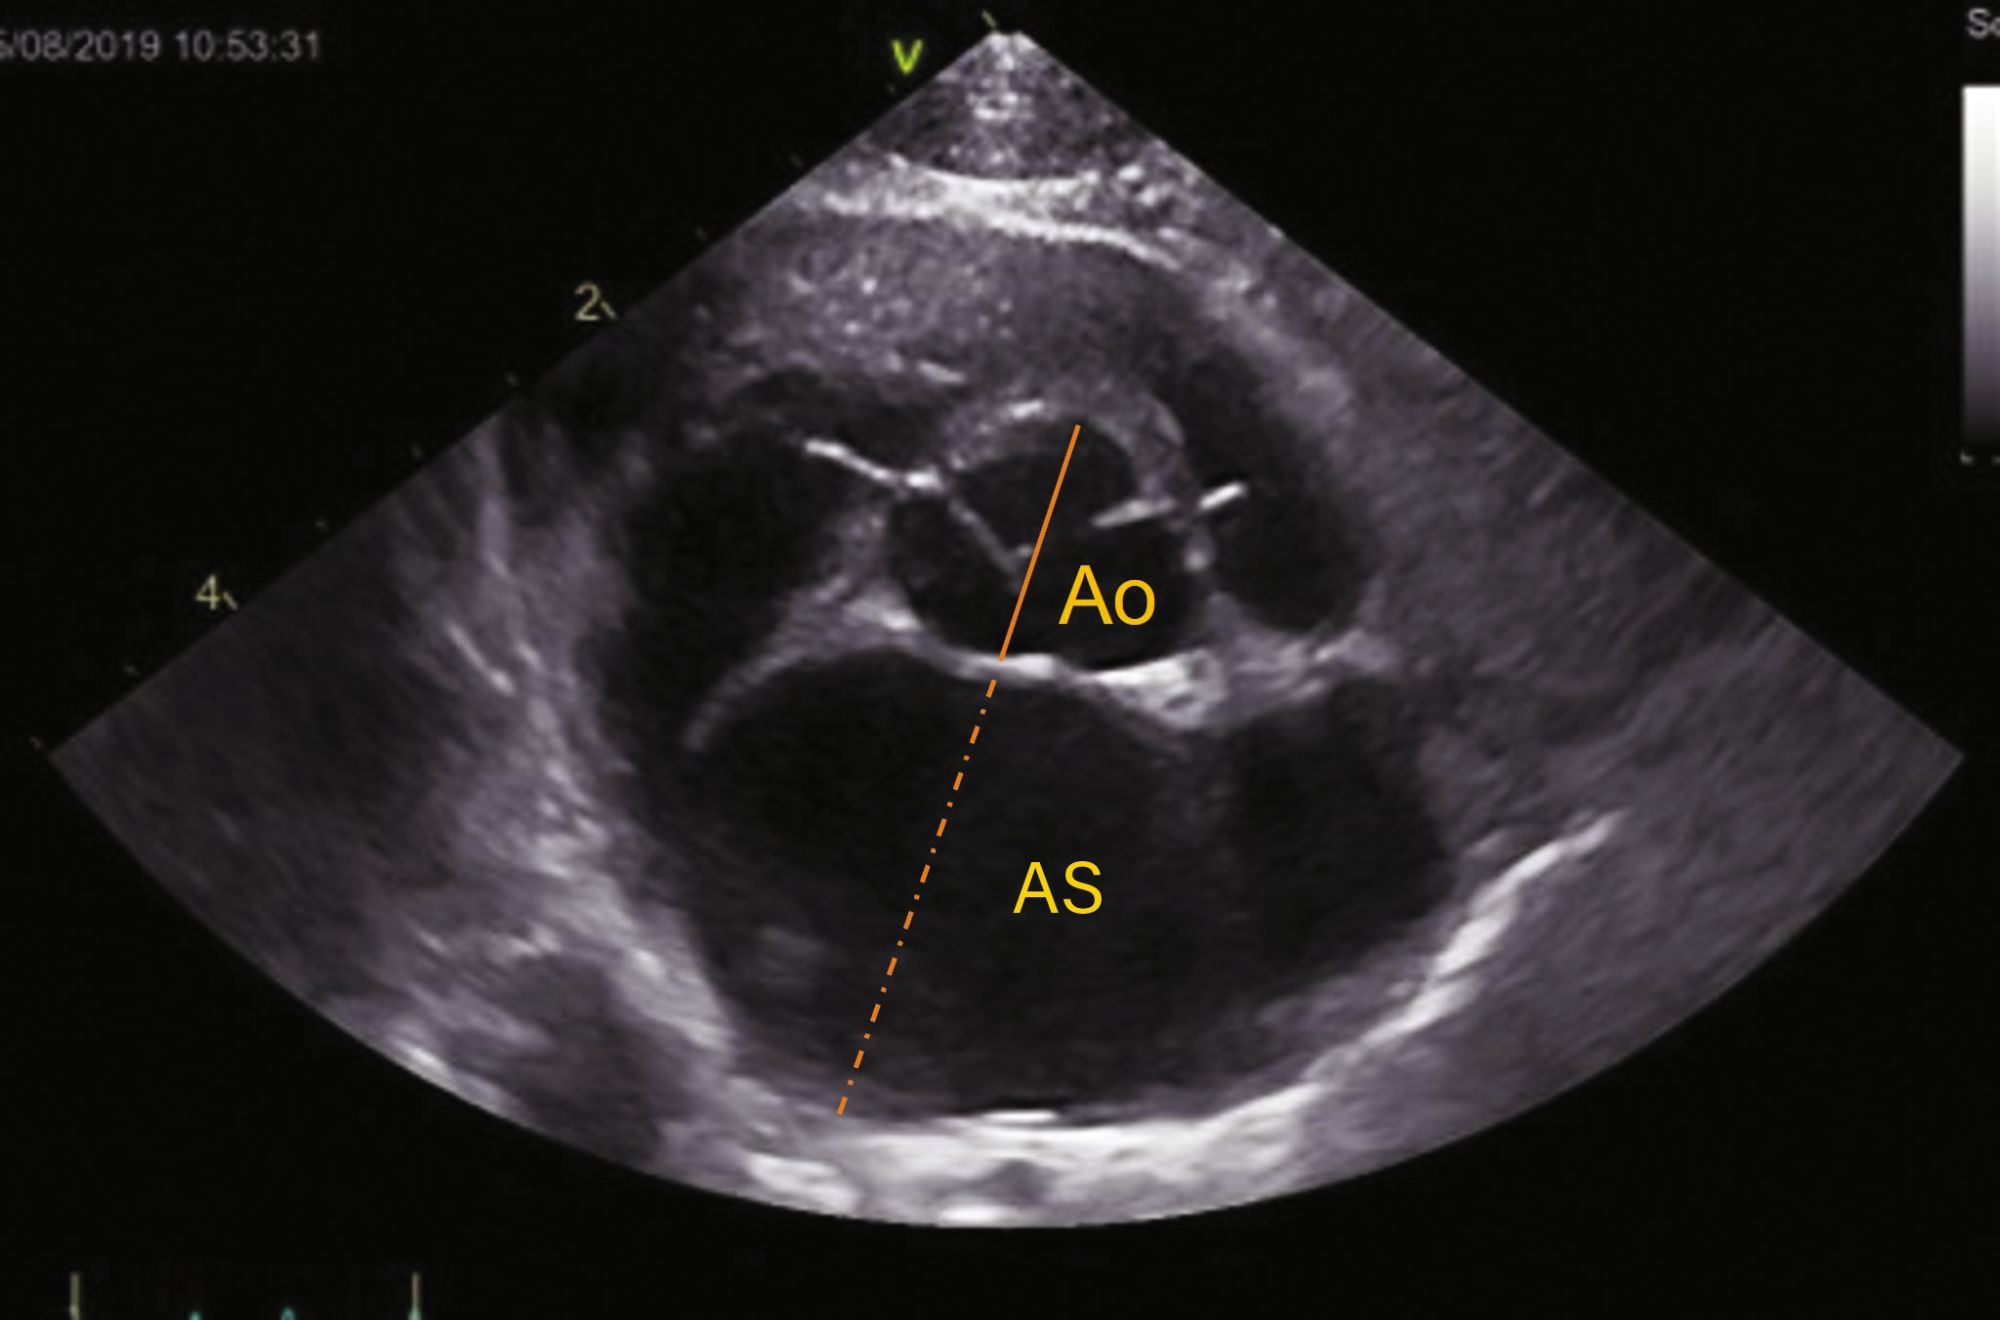

2. Dimensiunea atriului stâng

Dimensiunea AS este un factor de risc independent pentru ICC, TE și decesul cardiac și poate fi evaluat atât pe vizualizările parasternale drepte în ax lung, cât și în ax scurt. În vizualizările în ax scurt la baza inimii, măsurătorile se efectuează la debutul diastolei (cadrul de după închiderea cuspelor valvulare aortice), diametrul atrial fiind corelat cu aorta (LA/Ao în Figura 4b). Aorta se măsoară de la mijlocul curburii convexe a peretelui sinusului aortic drept până la punctul în care converg peretele aortic, cuspele aortice non-coronare și coronare stângi. AS se măsoară din acest ultim punct până la peretele liber al AS, evitând pătrunderea în vena pulmonară. [17].

Evaluare ecocardiografică a cardiomiopatiei hipertrofice (HCM).

Figura 4b. Evaluare ecocardiografică a cardiomiopatiei hipertrofice (HCM). Vizualizare parasternală dreaptă în ax scurt la baza inimii. Dimensiunea atriului stâng este corelată cu rădăcina aortică (AS/Ao), măsurată la debutul diastolei; valorile > 1,6 indică dilatarea atriului stâng.

Credit: Catheryn Partington Joanna Dukes-McEwan

În vizualizare parasternală dreaptă în ax lung cu patru camere, AS trebuie optimizat, iar diametrul atriului stâng (DAS) trebuie măsurat la finalul sistolei (cadrul anterior deschiderii foiței valvei mitrale), trasând o linie paralelă cu inelul mitral de la septul interatrial până la peretele liber al AS (Figura 4c) [18]. Un raport AS/Ao > 1,6 și DAS > 16,0 mm indică mărirea AS; valorile AS/Ao >1,8-2,0 sau DAS > 18-19 mm indică o mărire moderată până la severă a AS. Scurtarea fracționată a AS poate fi de asemenea determinată pentru a evalua funcția sistolică. Evaluarea subiectivă a dimensiunii apendicelui auricular stâng, prezența unui contrast ecocardiografic spontan sau a unui tromb și evaluarea vitezelor apendicelui auricular stâng sunt de asemenea factori importanți pentru analiza riscului de ICC și TE.

Figura 4c. Evaluare ecocardiografică a cardiomiopatiei hipertrofice (HCM). Vizualizare parasternală dreaptă în ax lung cu 4 camere. Diametrul atriului stâng este măsurat paralel cu inelul mitral la finalul sistolei; valorile > 16,0 mm indică dilatarea atriului stâng.

Abrevieri: Ao, aorta; IVS (SIV), sept interventricular; LA, atriul stâng (AS); LV, ventriculul stâng (VS); LVFW, peretele liber al ventriculului stâng; MV, valva mitrală (VM).